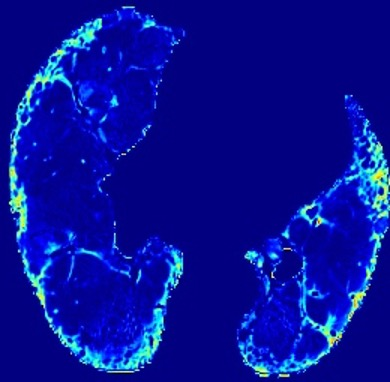

In the field of medical imaging, particularly in tasks related to early disease detection and prognosis, understanding the reasoning behind AI model predictions is imperative for assessing their reliability. Conventional explanation methods encounter challenges in identifying decisive features in medical image classifications, especially when discriminative features are subtle or not immediately evident. To address this limitation, we propose an agent model capable of generating counterfactual images that prompt different decisions when plugged into a black box model. By employing this agent model, we can uncover influential image patterns that impact the black model's final predictions. Through our methodology, we efficiently identify features that influence decisions of the deep black box. We validated our approach in the rigorous domain of medical prognosis tasks, showcasing its efficacy and potential to enhance the reliability of deep learning models in medical image classification compared to existing interpretation methods. The code will be publicly available at https://github.com/ayanglab/DiffExplainer.